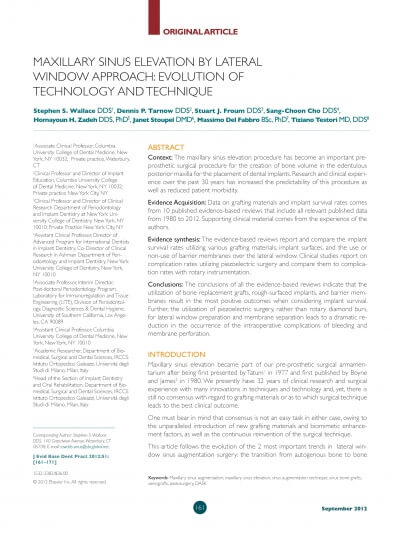

MAXILLARY SINUS AUGMENTATION- 3 CASES

SINUS FLOOR AUGMENTATION WITH HYDROPNEUMATIC TECHNIQUE

SINUS AUGMENTATION PROCEDURES